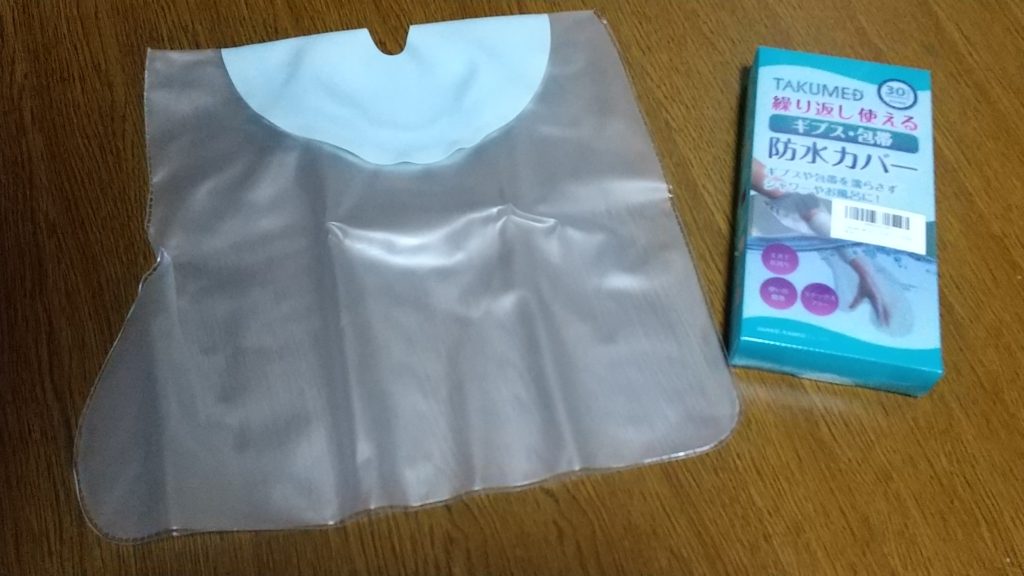

水濡れ防止グッズ

気になる「絶対濡らしてはいけない」対策。いまはこういうグッズがあるんですね。こんなのあるとは思わずにはじめはビニール袋で患部をカバーして濡れないよう片足立ちでシャワーしていました笑。

担当医師がはきはきしていらっしゃる方で、外来待ちの時、外まで「なんで濡らしたの?ダメって言ったでしょ」という叱りが聞こえてきたことがあったので必要以上にビビりました。ビニール袋だけでは物足りない。なんか対策せねば。そこで困った時のamazonを見てみました。

↑amazonアフィリですが、こんな感じです。購入したものは、湯船に入る用ではないですが、足首から下の部分がまるっとくるまれ、濡れずにシャワーを使うことができました。2,000円弱の出費で、安心してシャワーを使えるのはとてもありがたかった~。